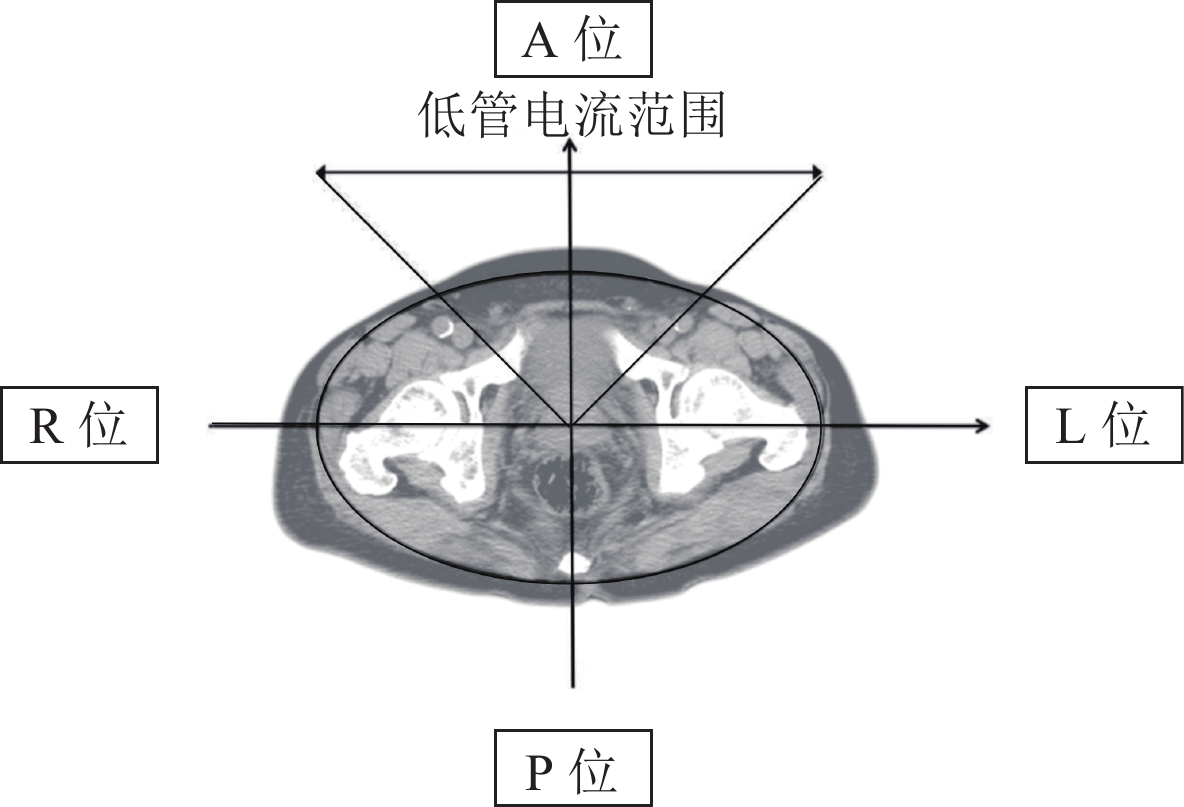

• 摘要: 目的:基于器官剂量调制(ODM)技术应用于男性盆腔电子计算机断层(CT)扫描中的探究。在不影响临床诊断的前提下,降低男性盆腔内组织器官所受有效辐射剂量,为将来应用此技术于男性盆腔疾病的流行病学大规模CT筛查,减少人群的辐射损伤提供理论基础。方法:运用随机对照临床试验,连续采集拟行盆腔CT扫描的成年男性受试者150例。将受试者按随机表法分为AODM组、BATCM组和CLOW组。AODM组CT扫描开启自动管电流调制(ATCM)技术基础上,同时开启ODM技术;BATCM组仅开启ATCM技术,其余扫描条件一致;CLOW组关闭ATCM技术,设置为固定管电流,其余条件一致。通过在受试者盆腔四方位,前、左、后、右安置DLVA-A CT伏安特性测试仪,测定并记录人体四方位管电流峰值。根据扫描后CT自动生成的辐射剂量表数据,计算出受试者所受有效剂量(ED)。依据AAPM220号报告计算SSDEprostate,估算出前列腺所受有效辐射剂量。选取盆腔内前列腺中心层面,在前列腺区域和臀大肌区域选取感兴趣区(ROI),比较客观噪声(SD)、信噪比(SNR)。在盆腔软组织窗下对重建所得横轴位和冠状位图像,进行李克特5分制主观评分。结果:客观测定数据显示,AODM组前方管电流显著低于BATCM组,具有显著统计学意义;其余方向无统计学差异。3组前列腺区域图像的SD、SNR水平之间两两比较,具有统计学意义;臀大肌区域的SD、SNR水平之间比较,AODM组和BATCM组无统计学意义。3组受试者经容积CT剂量指数(CTDIvol)估算出的单器官所受有效剂量(EDOS)和整体有效剂量(ED)差异均具有统计学意义。AODM组比较于BATCM组,管电流降低,有效剂量降低。主观评估结果显示,AODM组和BATCM组的横轴位和冠状位图像无统计学差异;CLOW组和AODM组、CLOW组和BATCM组的横轴位和冠状位图像均具有统计学意义。结论:与传统CT扫描方式相比较,器官剂量调制技术应用于男性盆腔电子计算机断层扫描中,在获得符合临床标准的医学影像前提下,可降低盆腔内辐射敏感器官的辐射强度,减少单器官和总体辐射有效剂量。

Abstract: Objective: Organ dose modulation (ODM) was used in male pelvic electronic computed tomography (CT) scans. To avoid affecting clinical diagnosis, the effective radiation dose of pelvic tissues and organs in men should be reduced to provide a theoretical basis for the future application of this technology in the epidemiological large-scale CT screening of male pelvic diseases and reduce radiation damage in the population. Methods: 150 adult male subjects with planned pelvic CT scans were selected in a randomized controlled clinical trial. In this study, the subjects were divided into AODM, BATCM, and CLOW groups according to the randomization table method. In the ODM group, the ODM utilized automatic tube current modulation (ATCM); only ATCM and the other scanning conditions were consistent; in the CLOW group, the ATCM was set to fixed tube current, and the other conditions were consistent. The peak human square tubular current was measured and recorded by placing the DLVA-ACT voltammetric characteristic tester in the anterior, left, posterior, and right sides. The effective dose (ED) was calculated from the radiation dose table data automatically generated after the CT scan. The effective radiation dose of the prostate was estimated by calculating SSDEprostate from the AAPM220 report. At the central level of the pelvic prostate, the region of interest (ROI) was selected in the prostate and gluteus muscle regions to compare standard deviation (SD) and signal-to-noise ratio (SNR). The reconstructed transaxial and coronal images were scored under the pelvic soft tissue window. Results: The objective data showed that the anterior tube current was significantly lower than that in the BATCM group; no statistical difference was observed in the other directions. Pairwise comparisons between the SD and SNR levels in the three prostate regions were statistically significant; the SD and SNR levels in the gluteus maximus region were not significant between the AODM and BATCM groups. The difference in the signal organ effective dose (EDOS) and overall effective dose (ED) between the volume CT dose Index (CTDIvol). Compared with the BATCM group, the tube current and ED in the AODM group decreased. Conclusion: Compared with traditional CT scanning, ODM is used in male pelvic electronic CT, which can reduce the radiation intensity of radiation-sensitive organs in the pelvic cavity and ED of single organs to obtain medical images that satisfy clinical standards.